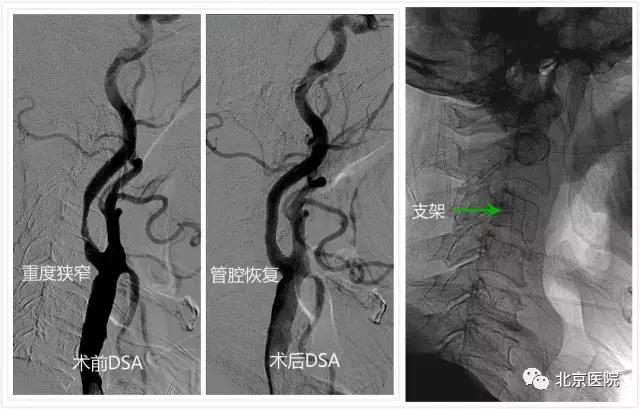

针对颈动脉狭窄,早在上世纪90年代,北京医院神经外科刘树山主任就开展了颈动脉内膜剥脱术;2002年,在国内最早报道了采用脑保护装置辅助进行颈动脉狭窄支架成形术。神经外科还与神经内科、放射科、超声医学科、核医学科等兄弟科室开展长期合作,围绕颈动脉狭窄患者的认知功能、脑血流灌注、颈动脉斑块稳定性等热点和难点问题,进行了深入的临床和基础研究;先后承担了原国家卫生部临床学科重点项目、首发基金项目、北京医院“121项目”等多项科研课题;发表相关学术论文30余篇;主办了大型脑血管病研讨会10余次。值得一提的是,作为国家老年医学中心,北京医院接诊的颈动脉狭窄患者一直以老年、高龄患者居多,仅在2016年,就治疗了老年颈动脉狭窄患者74例(占总数70%多),无一例出现严重手术并发症。